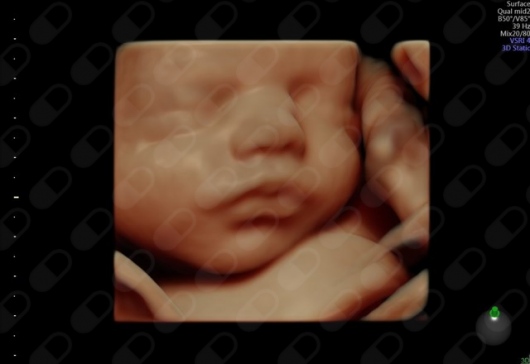

Ecografía 5D

El centro acaba de adquirir el mejor ecógrafo existente en el mercado, el ecógrafo Voluson E10 BT 2018, que permite realizar con máxima fiabilidad todas las ecografías de embarzo (1er, 2 trimestre, EBA-creening, 3er trimestre....) asímismo la 5HD LIVE y la novedísima eco 6D desde la primera hasta la última ecografía del embarazo por un precio muy asequible. Actualmente es el único ecógrafo existente en Barcelona, por lo que el centro se pone en primera linea de diagnóstico prenatal